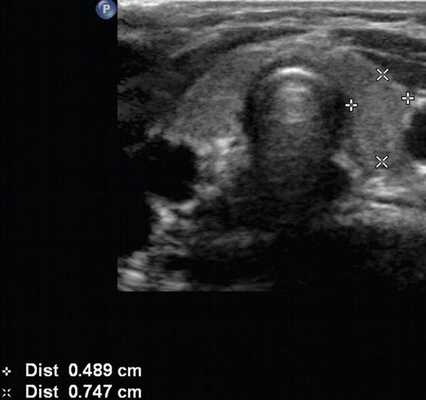

(Слева) УЗИ, поперечная проекция: визуализируются множественные солидные изоэхопенные узлы различного размера, имеющие однородную структуру, но без включений кальция. Большинство узлов окружены замкнутым гипоэхогенным ободком.

о Типичный МУЗ: множественные неоднородные узлы:

- Множественные узлы, двухстороннее диффузное поражение

- Солидные узлы часто изоэхогенны, малая часть узлов гипоэхогенны

- Тонкий и хорошо отграниченный гипоэхогенный «ободок»